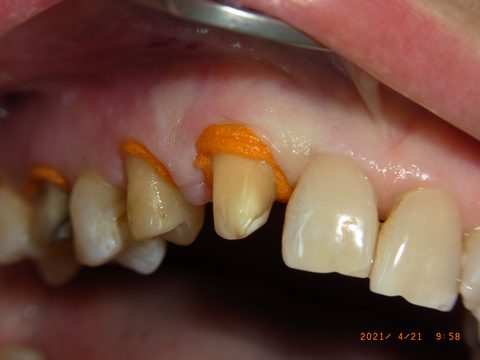

Gute Patienten- (durch Prophylaxe) und Sulcusvorbereitung (intragingivale, adrenalinhaltige Anästhesie, Faden Knit-Pak Gr. 2 (Fa. Premier) mit Racestyptine (Fa. Septodont), ca. 10 min Einwirkzeit) und möglichst knochentrockene Situation direkt vor der Abformung bleiben wichtig. (Anmerkung 7/2023: Die Abdruckspritze ist wieder dabei, weil sie die Luftblasen im Sulcus reduziert.)

Retraktionsfaden Knit-Pak Gr. 2 mit Racestyptine an den Frontzähnen des Oberkiefers: Der orange Faden öffnet den Sulcus für die anschließende Abformung.

Nahaufnahme: Der Faden liegt tief im Sulcus und verdrängt die Gingiva zuverlässig. Die knochentrockene Situation ist für eine fehlerfreie Sulcusabformung entscheidend.

Retraktionsfaden auch im Seitenzahnbereich. Die Abdruckspritze steht bereit, um unmittelbar nach Fadenentnahme mit der Zweitabformung zu beginnen.